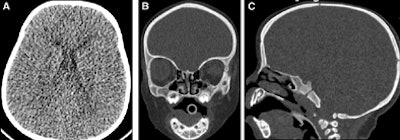

| Low-dose craniosynostosis CT protocol in a 1-year-old girl revealed telecanthus but no craniosynostosis. Scan parameters of 80 kVp and 50 mA resulted in an estimated effective radiation dose of 0.1 mSv. Images republished with permission of the American College of Radiology from JACR, August 2011, Vol. 8:8, pp. 591-593. |

In pediatric CT, children's thinner skulls mean that dose can be reduced even further (e.g., 80 kVp, 50 mAs) to obtain required diagnostic information at radiation doses of fractions of a millisievert, according to the authors. Optimal dose reduction is even more critical in applications such as shunt patency studies in children with ventriculoperitoneal shunting, who often undergo multiple repeat exams.

In children, for example, MRI is increasingly sought for head imaging, but CT is still preferred for certain indications such as acute trauma, stroke, hydrocephalus, and craniosynostosis.